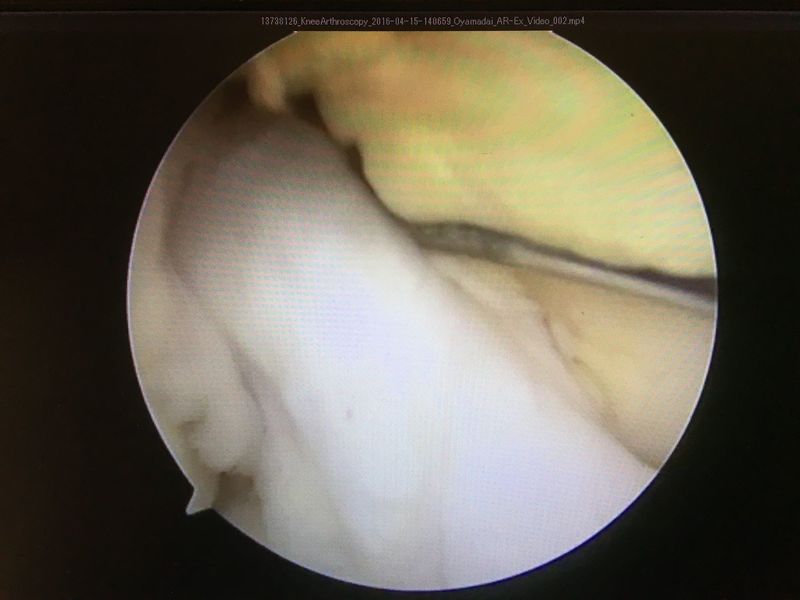

|

ACLは緊張がなく機能していない |

ACL再建

| 大腿骨孔作成 | グラフト挿入 | 再建靭帯 |

執刀医より

バレエの競技特性である美しさの獲得だけでなく、膝が完全伸展しないことは再受傷やパフォーマンス低下を招きます。 よって手術は膝が完全に伸びた状態でも前十字靭帯が前後・回旋に対して不安定性を生じないよう作り上げる必要があります。 この方は比較的経過が良好でした。バレエでの益々のご活躍を願っています。 |